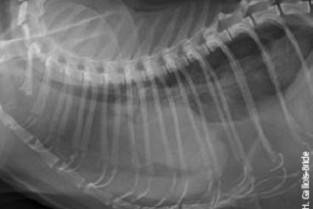

Avant, on « ouvrait pour voir ». Mais ça, c’était avant !

Maintenant, on « voit avant d’ouvrir». L’imagerie avant la chirurgie...

7 talentueux membres du GEIM et 5 conférenciers chevronnés du GEC vous emmèneront, au fil de cours théoriques et de travaux dirigés, explorer des affections thoraciques et abdominales ciblées. Les exposés seront résolument pratiques et cliniques, répartis sur 5 jours. Ne manquez pas ce rendez-vous unique, réputé pour son ambiance chaleureuse et sportive. GEIM le GEC !